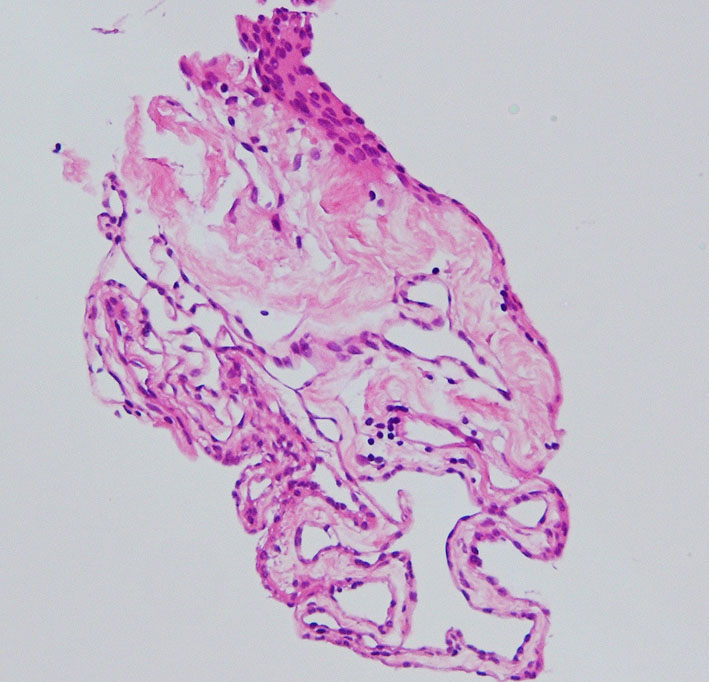

左の写真は,鞍上部から前橋槽の大きなのう胞の病理組織です。大きなのう胞でしたが薄いのう胞壁で取り出すとぺしゃんこになりました。

一層の上皮細胞がのう胞壁を構成します。薄い結合織や無機質な間質を介して内外壁があるものもあります。

コロイドのう胞,上皮嚢胞,上衣のう胞,ラトケのう胞は同じような病理所見です。発生部位と画像所見では鑑別できますが,病理検査では内胚葉のう胞 endodermal cystとしか診断がつきません。細胞表面にcilliaがあるかどうかでも診断は変わりません。

のう胞壁の組織像は大部分が線維性に肥厚した結合織膜でした。裂け目のように見えるのはコレステロール choresterol crystalが抜けた部分です。その間に異物巨細胞(黄色の矢印)が多数見られます。のう胞内容が古い血腫でしたから, ヘモジデリンを貪食したマクロファージ (CD68+)が見られ慢性炎症所見です。病理診断としては,コレステロール肉芽腫 chorelsterol granulomaとなります。免疫組織染色でCam5.2陽性の細胞があり扁平ないし立方上皮を形成していました。病理診断では,第3脳室コロイドのう胞が変性消褪して瘢痕化した病変と結論付けられました。